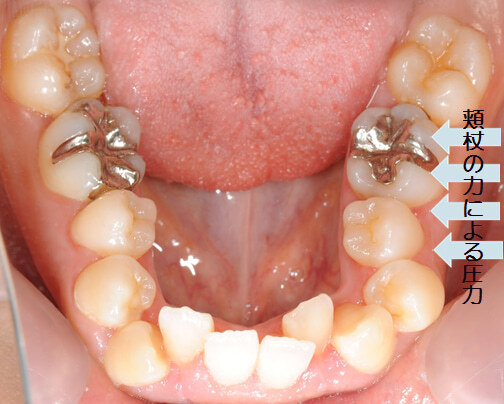

例えば、頬杖をしている人の歯並びはこのように変形してしまいます。